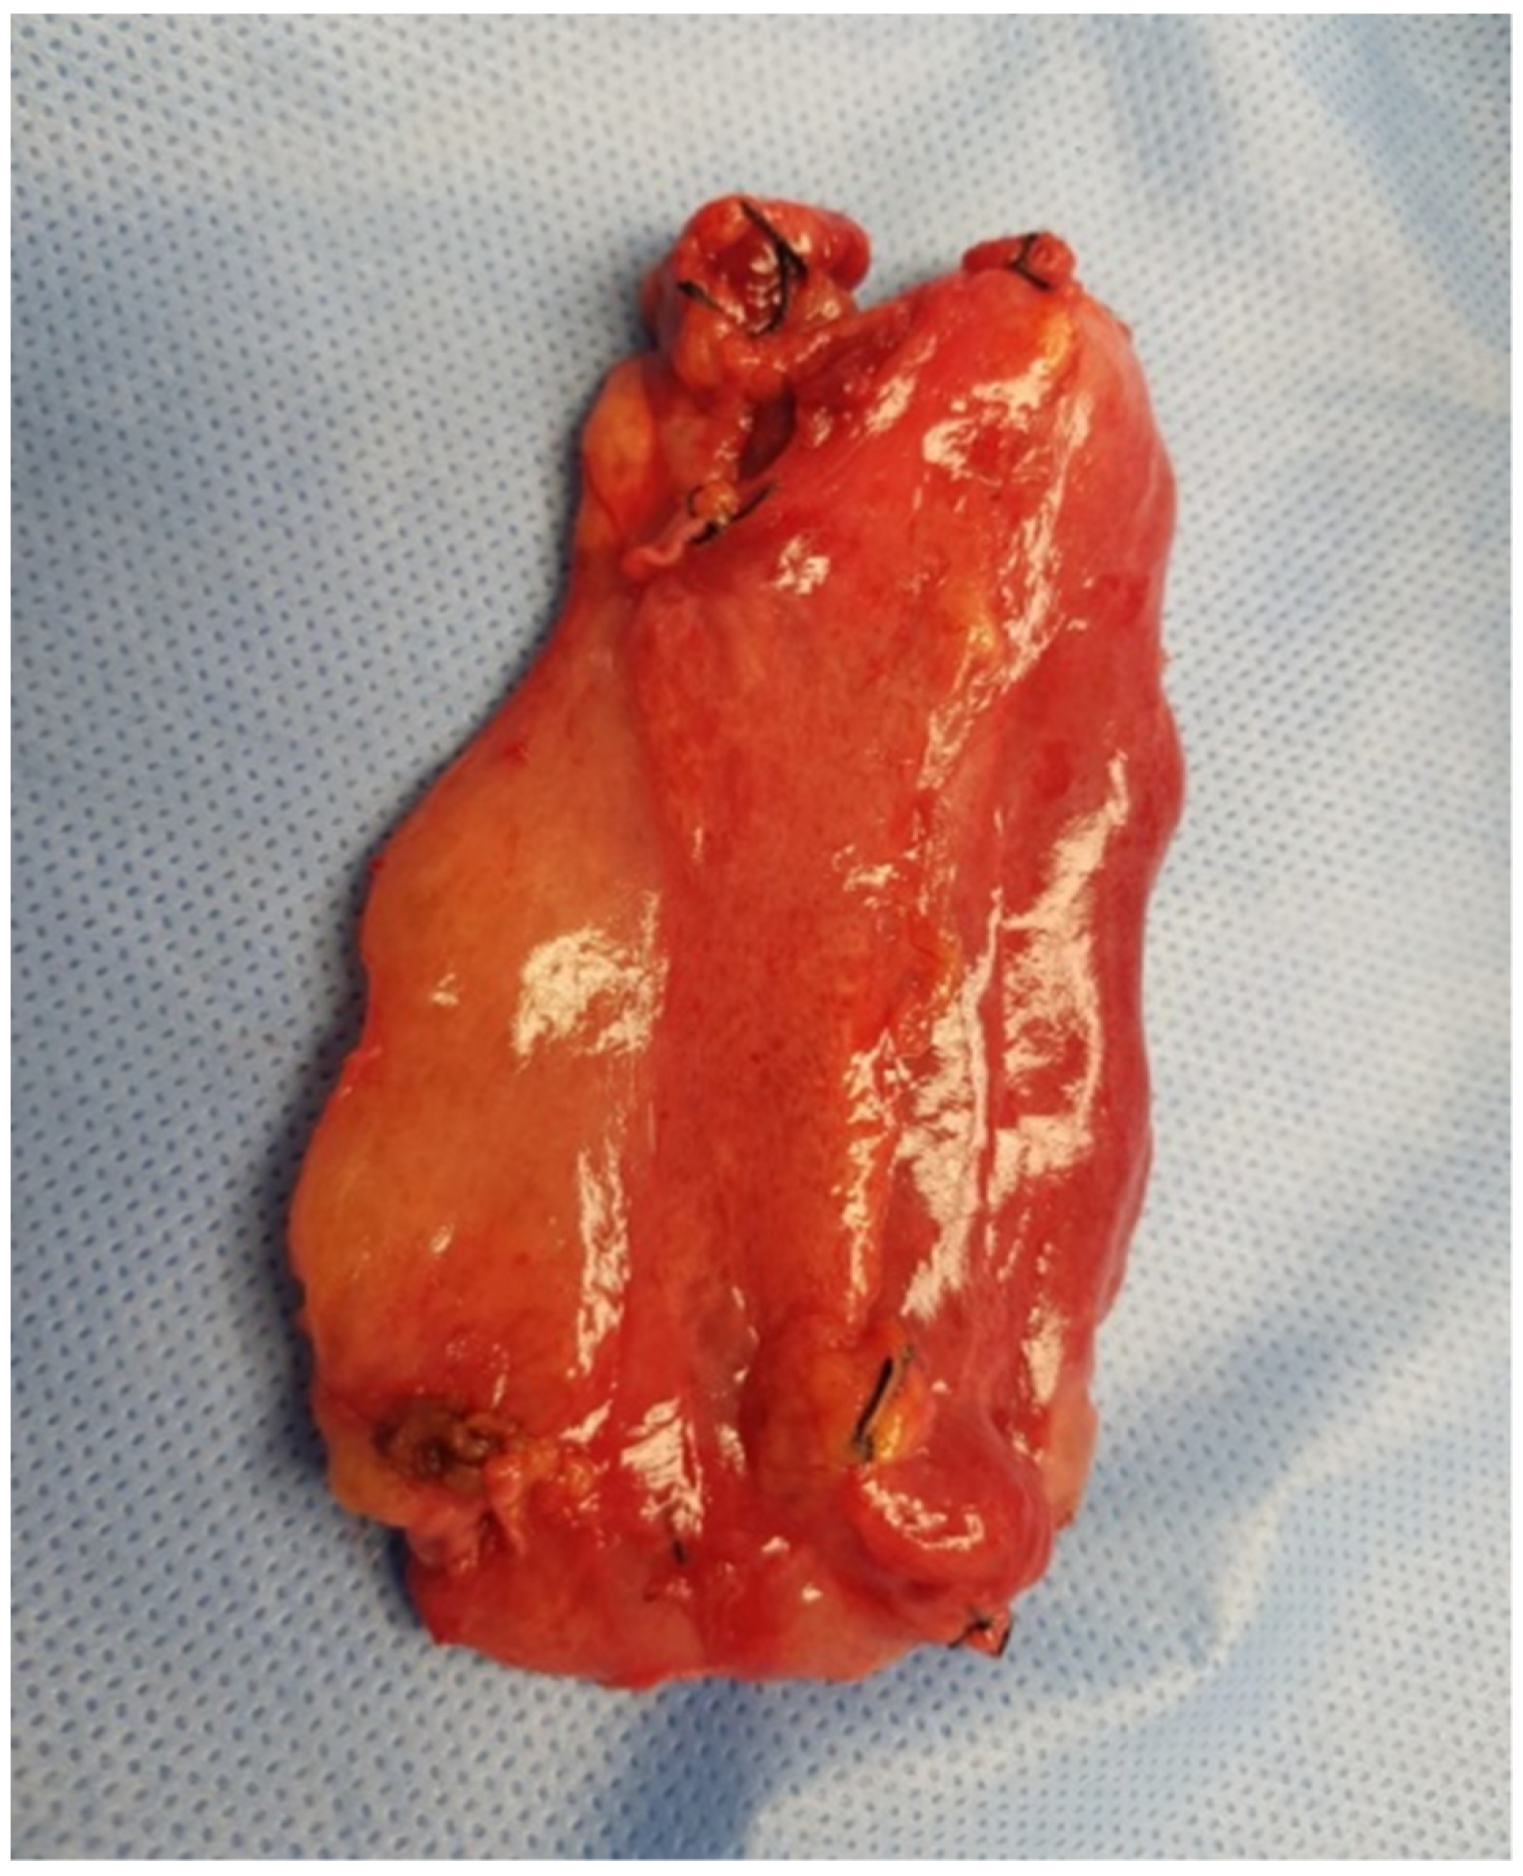

The patient was qualified for elective surgery. The presence of an approximately seven-cm long soft tissue extending along the lesser curvature of the stomach, closely connected to the stomach wall, was found intraoperatively (Figure 2). The tumour penetrated the gastrohepatic ligament, but did not reach the liver. The lesion did not penetrate the retroperitoneal space or infiltrate the pancreas. The tumour was completely removed without gastric wall resection (Figure 3). After removal of the lesion, the serosa of the lesser curvature of the stomach was secured with a continuous PDS 4/0 suture (Figure 4).

Figure 3. The excised specimen following the operation. The size of the specimen is 7 × 5 cm.